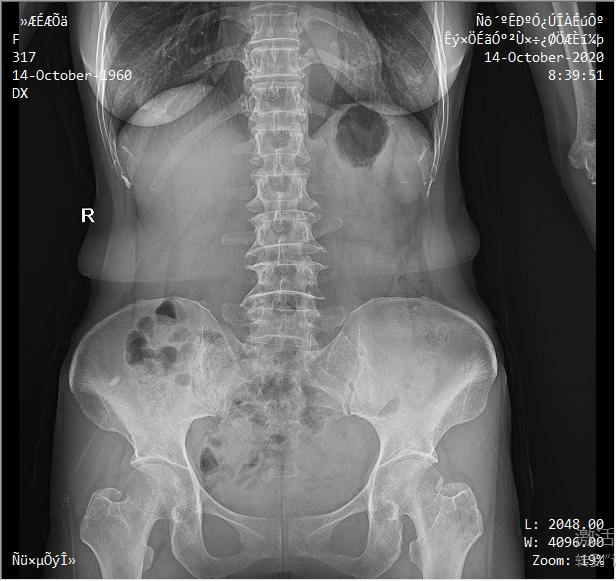

● 圖像預處理

依據臨床圖像庫自動進行圖像后處理,呈現效果佳。